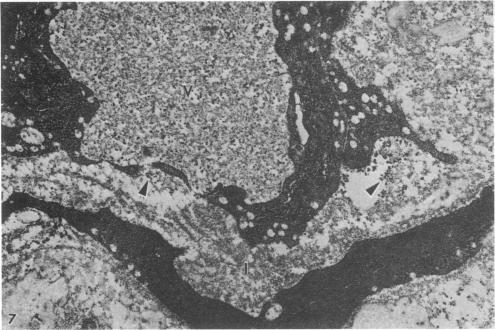

Interleukin-1 (IL-1) mediates components of the acute-phase response, stimulates granulocyte metabolism, and induces endothelial cell surface changes. We studied the effects of human recombinant IL-1 beta (rIL-1 beta) or rIL-1 alpha on circulating granulocytes, their sequestration within the pulmonary microvasculature, pulmonary edema formation, and changes in pulmonary vascular permeability to 125I-labeled albumin. rIL-1 beta administration induced significant (P less than 0.03) but transient granulocytopenia followed by significant (P less than 0.04) neutrophilia and significant (P less than 0.04) pulmonary leukostasis compared with saline-infused rabbits. Rabbits preinfused with 125I-labeled rabbit serum albumin and administered saline, rIL-1 beta, or rIL-1 alpha were sacrificed, and lung wet/dry weight ratios and bronchoalveolar lavage fluid and plasma 125I activities determined. Both rIL-1 beta and rIL-1 alpha increased lung wet/dry weight ratios (P less than 0.025 and P less than 0.01, respectively) compared with saline controls. rIL-1 beta increased bronchoalveolar lavage fluid/plasma 125I radioactivity ratios (P less than 0.025). Electron microscopic analysis of lung sections obtained from rIL-1 beta-infused animals demonstrated endothelial injury, perivascular edema, and extravasation of an ultrastructural permeability tracer. The observation that human rIL-1 can evoke acute pulmonary vascular endothelial injury and lung edema in rabbits supports the hypothesis that IL-1 may play a role in the pathogenesis of the adult respiratory distress syndrome.

白细胞介素-1(IL-1)介导急性期反应的组成部分,刺激粒细胞代谢,并诱导内皮细胞表面变化。我们研究了重组人IL-1β(rIL-1β)或rIL-1α对循环粒细胞的影响、它们在肺微血管系统中的滞留、肺水肿形成以及肺血管对125I标记白蛋白的通透性变化。与输注生理盐水的兔子相比,给予rIL-1β可导致显著(P<0.03)但短暂的粒细胞减少,随后是显著(P<0.04)的中性粒细胞增多和显著(P<0.04)的肺白细胞淤滞。对预先输注125I标记兔血清白蛋白并给予生理盐水、rIL-1β或rIL-1α的兔子进行处死,测定肺湿/干重比以及支气管肺泡灌洗液和血浆中的125I活性。与生理盐水对照组相比,rIL-1β和rIL-1α均增加了肺湿/干重比(分别为P<0.025和P<0.01)。rIL-1β增加了支气管肺泡灌洗液/血浆125I放射性比值(P<0.025)。对接受rIL-1β输注的动物的肺切片进行电子显微镜分析显示有内皮损伤、血管周围水肿以及超微结构通透性示踪剂的外渗。重组人IL-1可在兔子中引发急性肺血管内皮损伤和肺水肿这一观察结果支持了IL-1可能在成人呼吸窘迫综合征发病机制中起作用的假说。